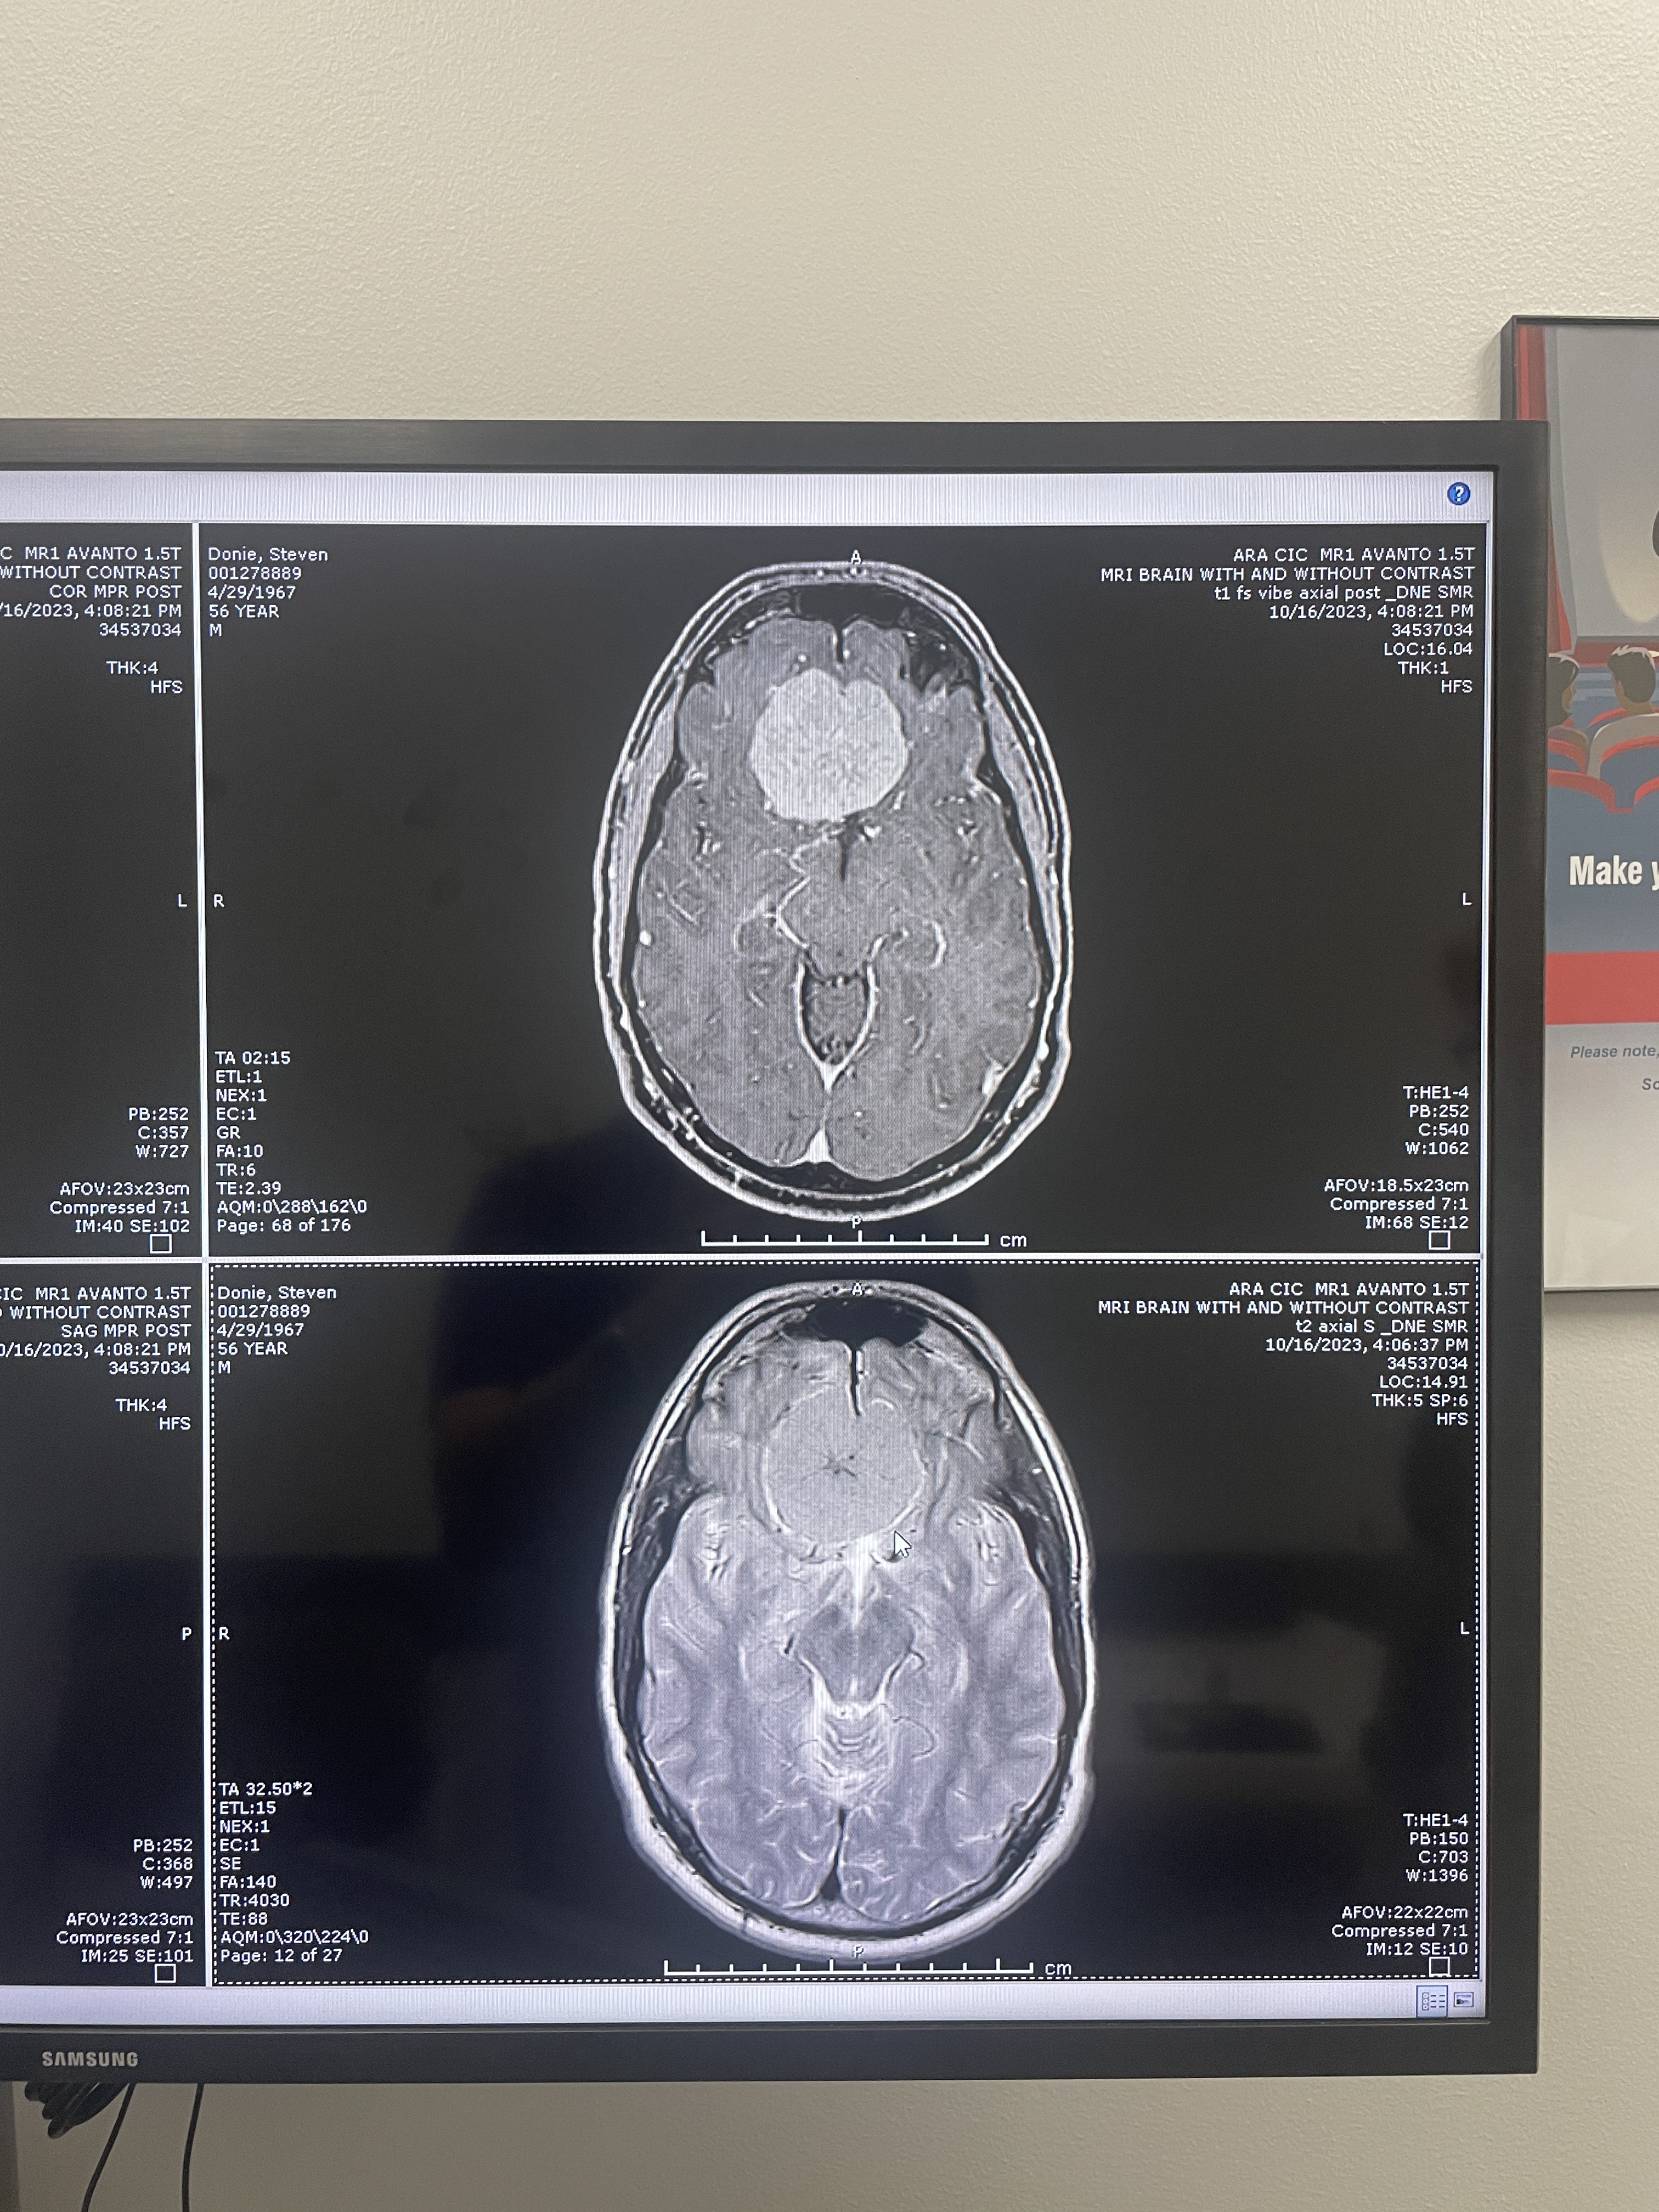

Another clear top view

more MRI